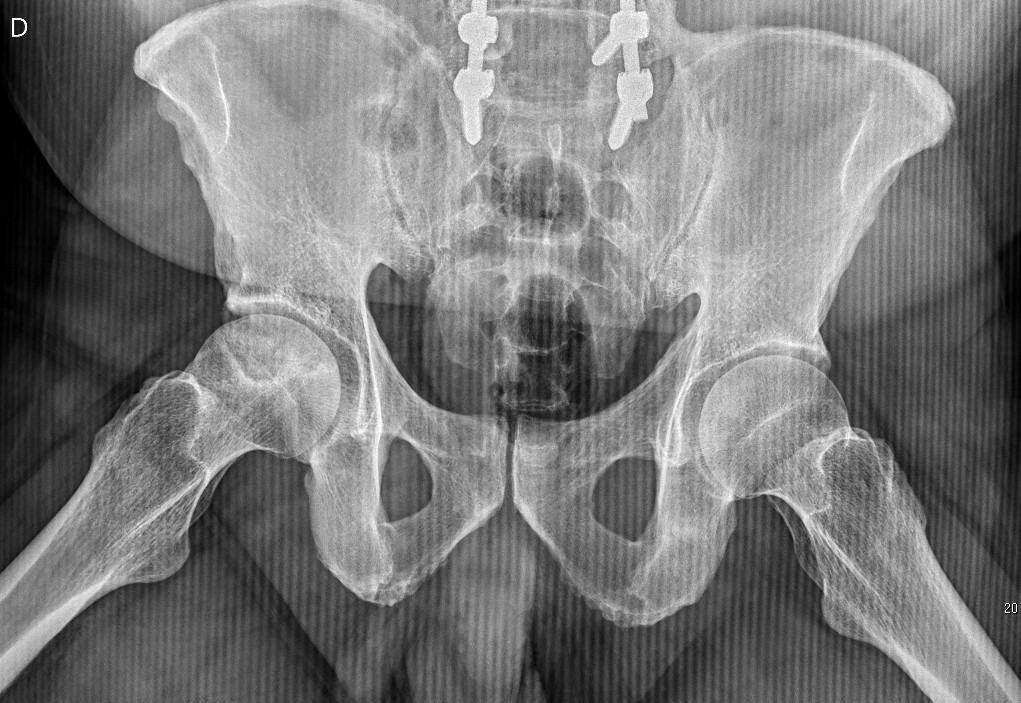

JuanMiranda

JuanMiranda@themskarchive·

Axial view.

JuanMiranda tweet media